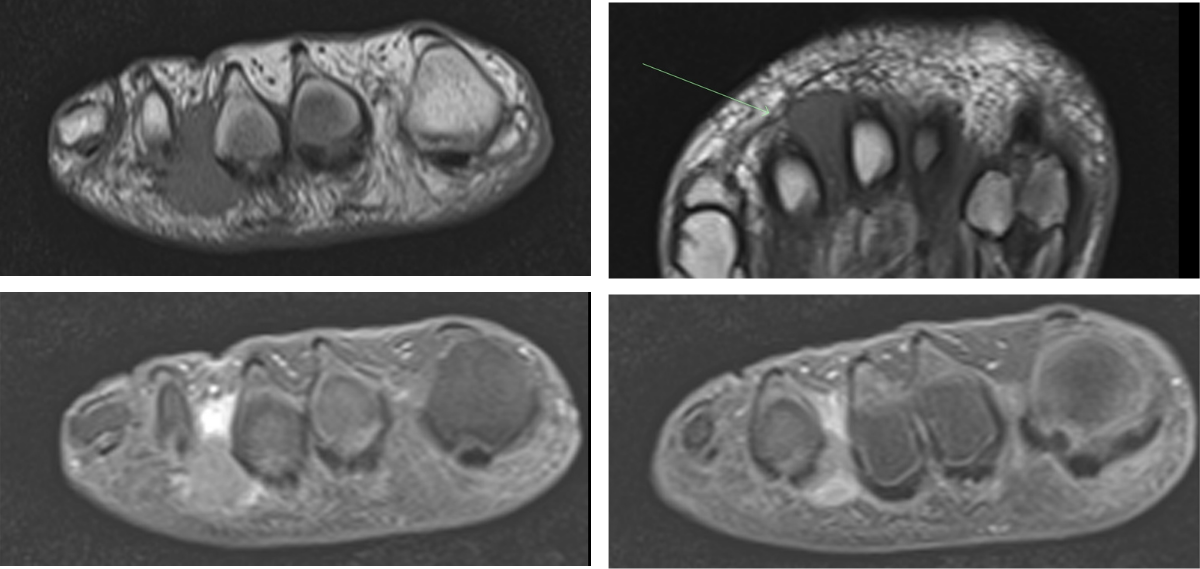

This finding represents a compressive neuropathy of the interdigital nerve primarily in the 2nd and 3rd intermetatarsal spaces.

Morton’s Neuroma

Presents with radiating pain, throbbing, numbness, and burning from the webspace into the toes. (Walking on marbles.)

Differential diagnosis: fracture, osteonecrosis, bursitis, synovial cyst.

Can have concomitant intermetatarsal bursitis.

AKA Intermetatarsal perineural fibrosis.

Takeaway: Common cause of forefoot pain – best seen on T1 weighted sequences.